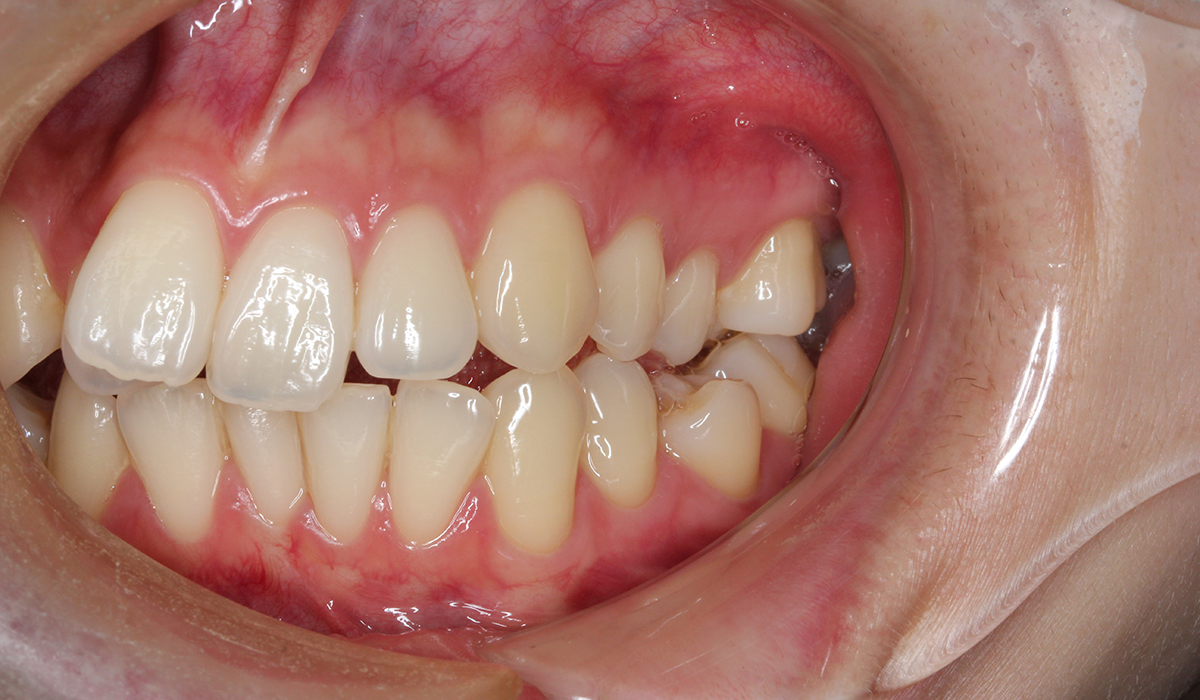

右側

BK終了時